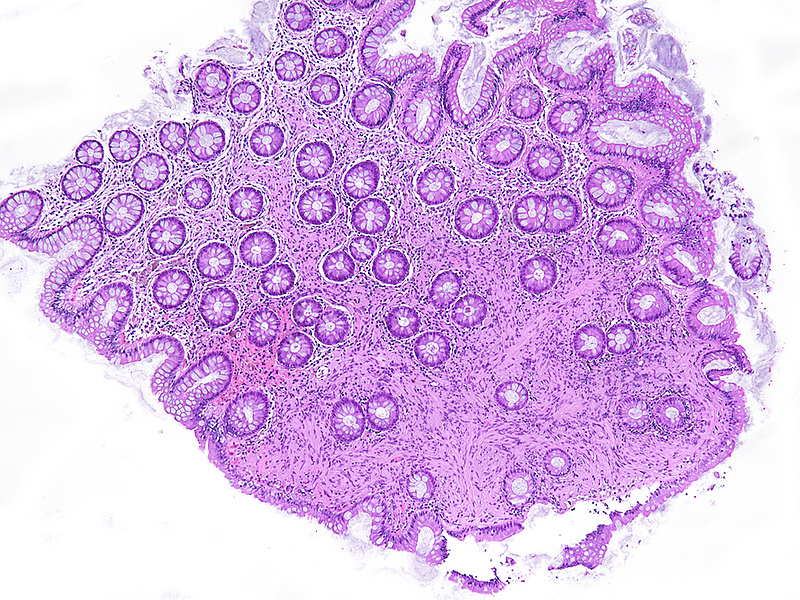

Small polyp in the sigmoid colon of a 75-year-old female.

Schwann cell hamartoma.

A dome-shaped sessile polypoid lesion with smooth glassy surface was removed from the sigmoid colon by forceps biopsy. Histology showed an expansion of the lamina propria by a diffuse proliferation of uniform bland-looking spindle cells with elongated tapering nuclei, abundant dense eosinophilic cytoplasm, and indistinct cell borders (Panels A-B). Colonic crypts were entrapped by the lesion. No nuclear atypia, pleomorphism, mitotic activity, or associated ganglion cells were observed (Panel C). The spindle cells were strong and diffusely positive for S-100 protein (Panel D).